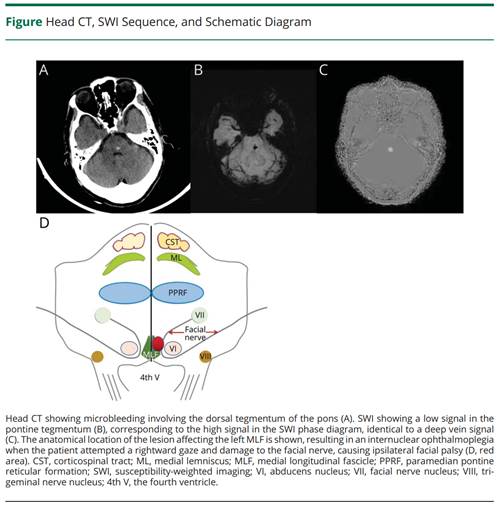

谭红团队在美国神经病学会刊《Neurology(神经病学)》上发表研究成果

近日,谈球吧附属长沙医院神经医学中心主任谭红教授团队,通过对一例脑桥微出血患者罕见临床表现的仔细观察,发现患者临床表现符合孤立的Seven-and-a-Half Syndrome(七个半综合征),通过检索Pubmed仅发现1篇相关报道。孤立的Seven-and-a-Half Syndrome临床极其罕见,但该综合征具有重要的临床解剖定位意义,因为病灶非常小,临床上极易因为影像学的阴性结果而被漏诊和误诊。最终该病例研究以教学影像视频的形式发表在国际神经病学TOP期刊《Neurology(神经病学)》,IF=10.1,中科院一区TOP期刊。

原文链接:https://www.neurology.org/doi/10.1212/WNL.0000000000207903?url_ver=Z39.88-2003&rfr_id=ori:rid:crossref.org&rfr_dat=cr_pub%20%200pubmed